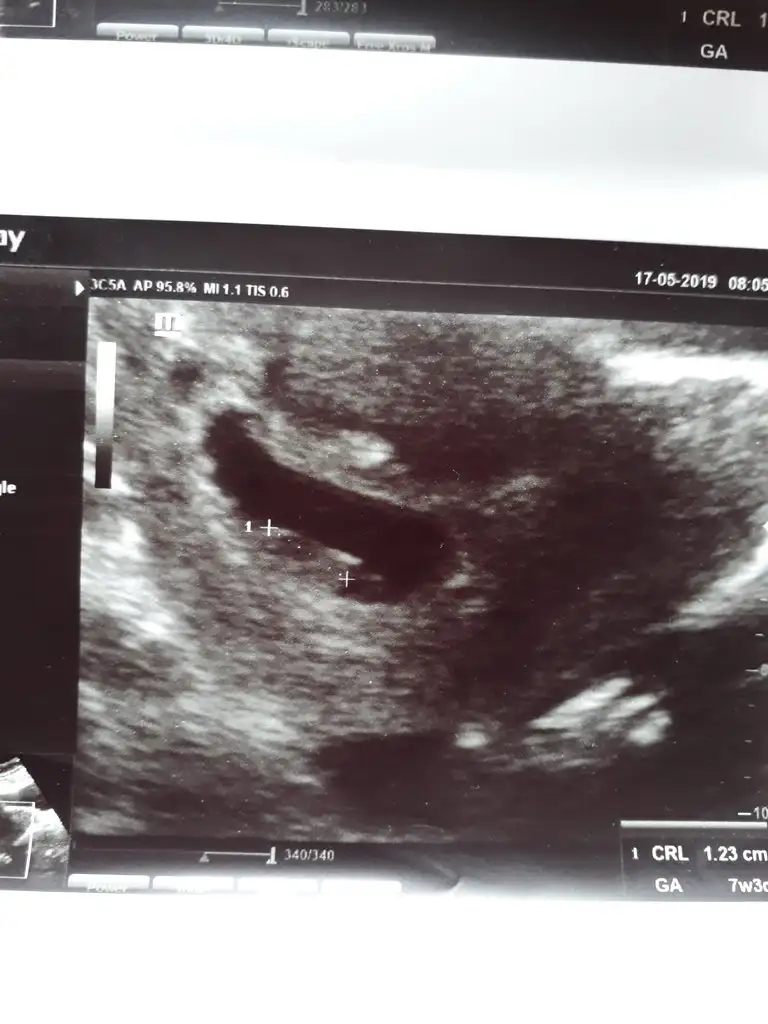

Kizlar banada yorum lutfen 1.resim 6 haftalik vajinal

2.resim 7 haftalik karindan usg